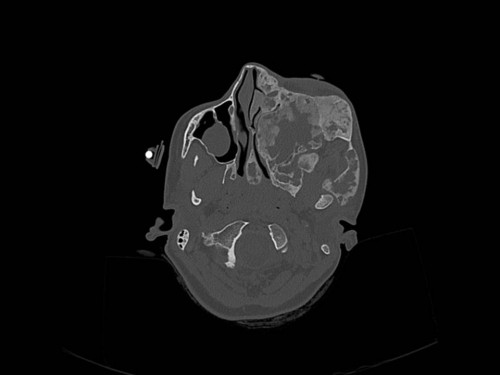

Knochendeformitäten seit der Geburt

Fall-ID: 712

ICD: M85.09

Autor*in: Sandra Klipp

Eine 16-jährige Patientin kommt in eine MKG-chirurgische Praxis zur Abklärung der weiteren Vorgehensweise bzgl. ihrer Erkrankung.

Sie betrachten die angefertigten Röntgenbilder. Welche der folgenden Röntgenbefunde ist korrekt? Ossäre Auftreibungen im Bereich …

- A… der Mandibula links.

- B… des Os frontale links.

- C… des Os zygomaticum links.

- D… des Os temporale links.

- EAlle genannten Aussagen sind korrekt.

Bildgebung - OPAN 2004